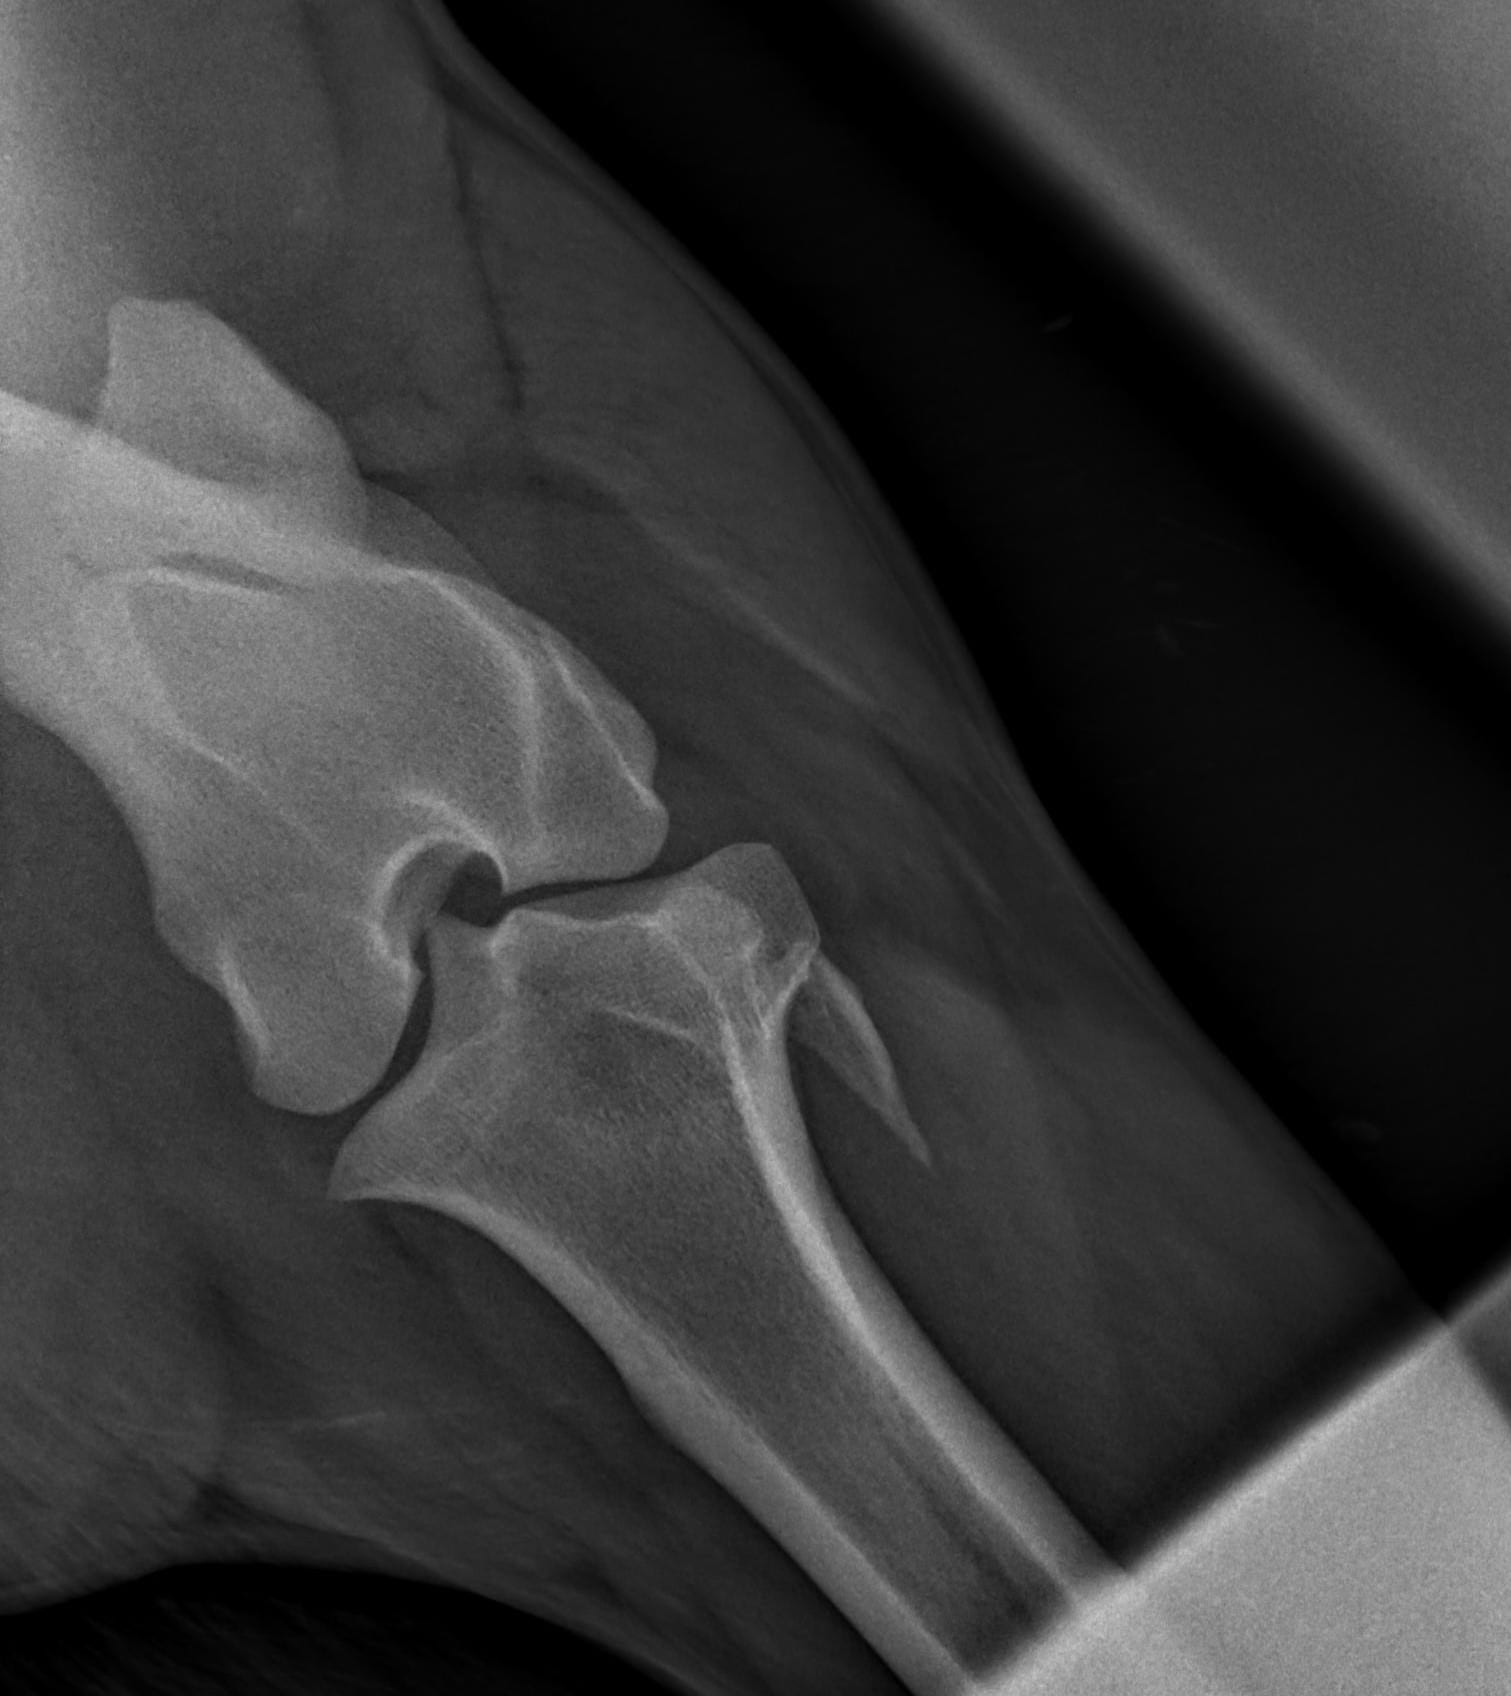

Bij onderzoek naar een stoornis aan het bewegingsapparaat wordt röntgen intensief gebruikt. Röntgenonderzoek laat veranderingen zien zoals kreupelheid, fracturen, botontstekingen en standsafwijkingen. Ook aanhechtingsproblemen van pezen en banden met botafwijkingen zijn in beeld te brengen. Daarnaast wordt röntgenonderzoek gebruikt bij problemen aan het hoofd en het gebit. Bij onderzoek naar problemen aan de luchtwegen kunnen röntgenfoto’s gebruikt worden voor het stellen van een diagnose. Voor een röntgenonderzoek wordt het paard onder lichte verdoving gebracht, zodat deze keurig stil staat en minder onder de indruk is van alle apparatuur. Om problemen in beeld te brengen zijn vaak meerdere röntgenfoto’s van dezelfde locatie noodzakelijk.